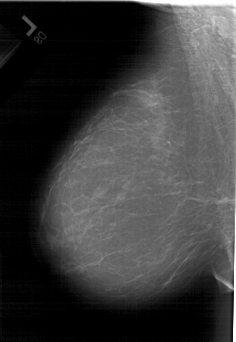

A_1440_1.LEFT_CC

LEFT_CC LINES 6586 PIXELS_PER_LINE 4351 BITS_PER_PIXEL 12 RESOLUTION 43.5 NON_OVERLAY